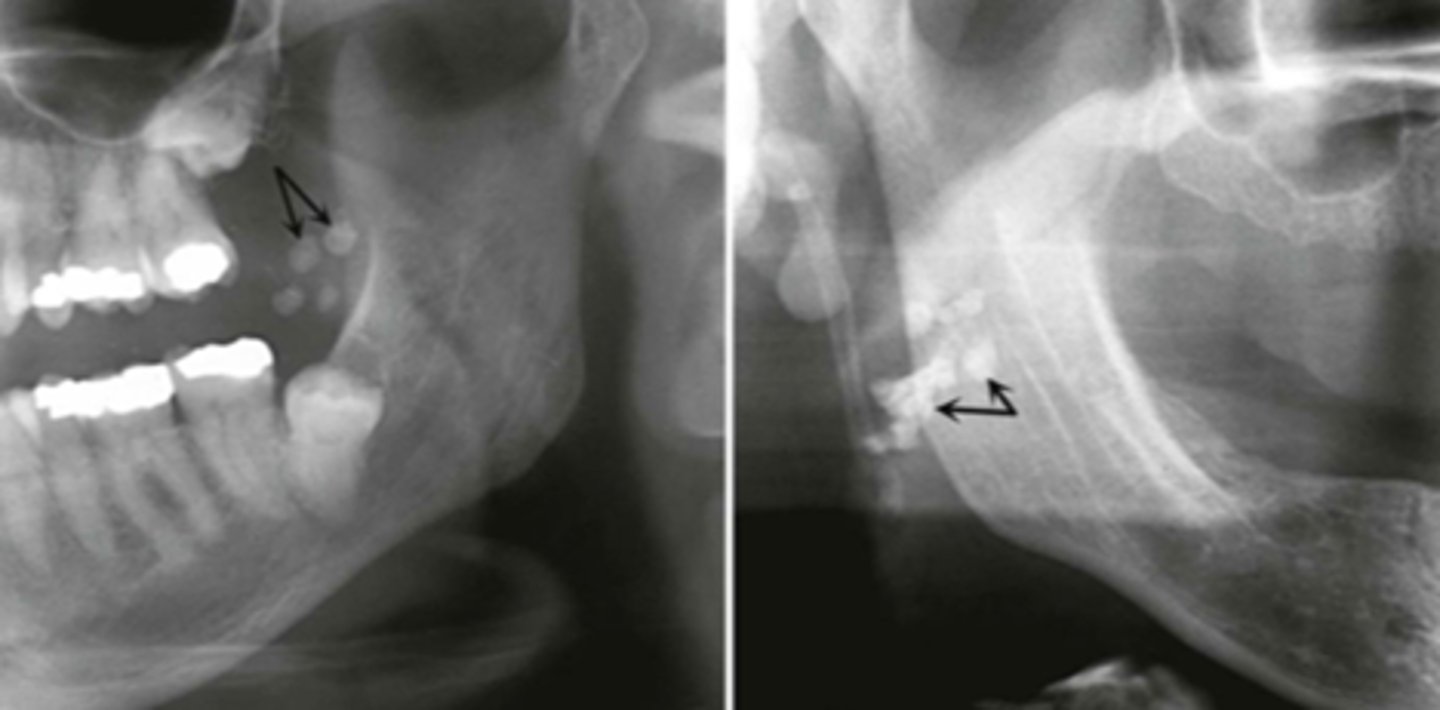

What area does odontogenic keratocyst (OKC) expand?

Mandibular posterior area

How does odontogenic keratocyst (OKC) expand around teeth?

Around entire tooth

What is the recurrence rate of odontogenic keratocyst (OKC)?

High recurrence rate

What are the differential diagnoses for odontogenic keratocyst (OKC)?

Ameloblastoma, dangerous cyst